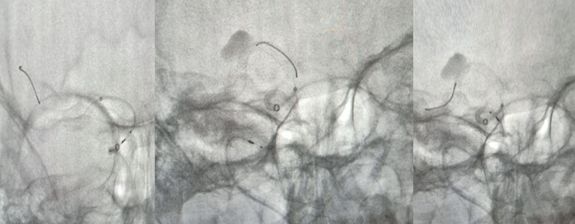

术前造影:

治疗过程简述

1、造影后显示右侧大脑中动脉M1段动脉瘤,路径图引导下由Traxcess(0.014,200 cm)微导丝携带Marksman支架微导管超选进入右侧大脑中动脉M2段远端(图一)。

图一